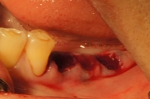

抜歯即時インプラント埋入・即時仮修復症例

奥歯三本が歯周病と根の破折で抜歯に。

入れ歯は絶対に嫌で歯がない期間があるのは困るとのご希望。

術前CT診断から後ろの二本なら抜歯直後にインプラント埋入が可能、後ろの一本は軽い骨移植が必要なので不可でしたが、前の一本は手術と同時に仮歯を入れることが可能と判断。

一度の処置で、抜歯・インプラント埋入・骨移植・仮歯まで行った症例。

抜歯後に骨移植を行いインプラントを入れる方法では治療期間が7~8か月かかるところをこの方法にしたので、入れ歯も使わずに治療期間を4か月に短縮できました。

被せ物の色は後日ホワイトニングを行うので白めにしています。